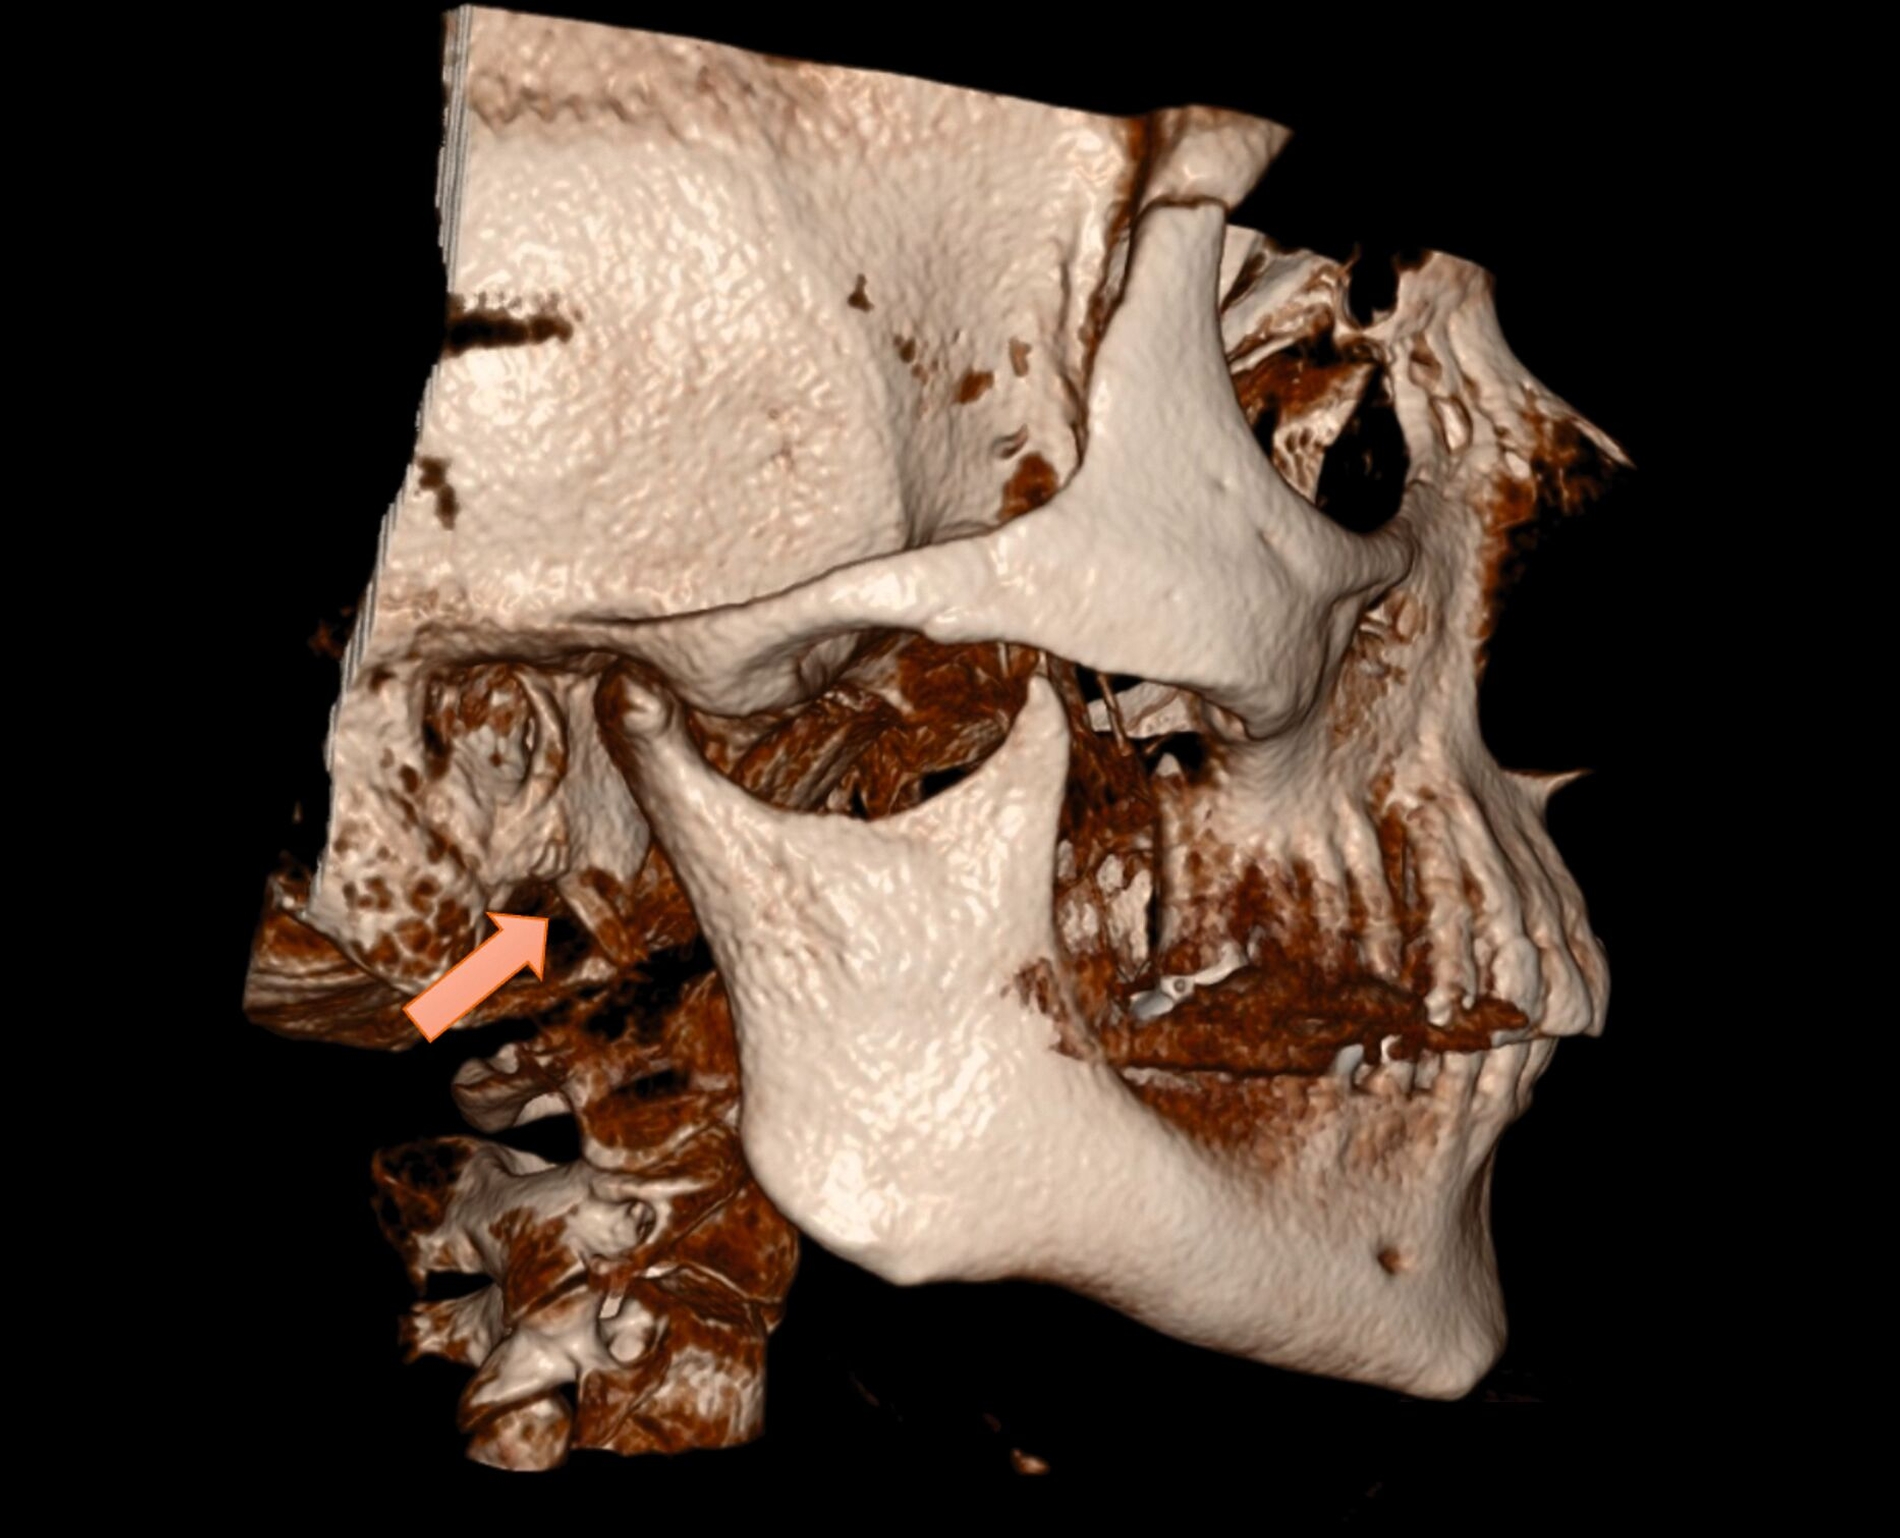

Die klinische Untersuchung ergab keine Hinweise auf Sensibilitätsstörungen, eine Fazialisparese oder Hirnnervenausfälle. Allerdings war die Palpation des rechten Kieferwinkels schmerzhaft, insbesondere bei der intraoralen Untersuchung der Tonsillenloge. Eine mechanische Provokation durch Kopfdrehung und Palpation verstärkte die Beschwerden. Die prothetisch versorgten Zähne zeigten keine pathologischen Befunde. Zur weiteren Diagnostik wurde eine Digitale Volumentomografie (DVT) mit 3D-Rekonstruktion durchgeführt. Diese bestätigte die im OPG vermutete Diagnose eines beidseitig elongierten Processus styloideus, mit einer stärkeren Ausprägung auf der rechten Seite (Abbildung 2).

Die klinischen Beschwerden korrelierten mit der radiologisch festgestellten Asymmetrie. Nach ausführlicher Aufklärung über konservative und operative Therapieoptionen entschied sich die Patientin aufgrund der deutlichen Symptomatik für eine chirurgische Resektion des elongierten Processus styloideus auf der rechten Seite. Der Eingriff wurde über einen extraoralen Zugang durchgeführt, um eine bessere Übersicht und die sichere Entfernung des verlängerten Processus zu gewährleisten. In Intubationsnarkose erfolgte die piezochirurgische Resektion des ossifizierten Ligamentum stylohyoideum am Processus styloideus über einen zervikalen Zugang (Abbildungen 3 bis 6); der ebenfalls verlängerte linke Ligamentum stylohyoideum wurde manuell von enoral frakturiert.

Die Diagnostik des Eagle-Syndroms basiert auf einer Kombination aus Anamnese, klinischer Untersuchung und bildgebenden Verfahren. Als Erstuntersuchung ist ein OPG geeignet, liefert jedoch keine detaillierten Informationen über die räumliche Lage des verlängerten Processus styloideus. Daher gilt die dreidimensionale Bildgebung (CT oder DVT) als Goldstandard, um die exakte Länge und die Beziehung zu den angrenzenden Strukturen zu bestimmen [Mortellaro et al., 2002]. Differenzialdiagnostisch müssen Kiefergelenkpathologien, eine Trigeminusneuralgie und psychosomatische Ursachen ausgeschlossen werden, was jedoch durch eine bildgebende Diagnostik zuverlässig möglich ist [Kozakovičová et al., 2023].

Die CT oder die DVT mit 3D-Rekonstruktion sind der diagnostische Goldstandard, da sie eine präzise Beurteilung der Länge und der Lage des Processus styloideus ermöglichen.